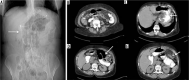

Material and methods: We retrospectively review 954 obese patients who underwent bariatric surgery between 2013 and 2019. The study included 72 patients who developed clinical suspicion of acute complications (painful and meteoric abdomen, nausea, vomiting, fever, intestinal blockage) within 6 days of bariatric surgery of sleeve gastrectomy, gastric banding, gastric bypass with Roux loop confirmed by CT, and who underwent a gastrointestinal transit before the CT examination.

Results: GI exam allowed visualisation of 58% of complications. Analysing the data for each surgical technique, 46 post-operative complications were found involve gastric banding. The most frequent was bandage migration (26 cases, 56 %), identified in all cases at GI transit and then confirmed on CT.